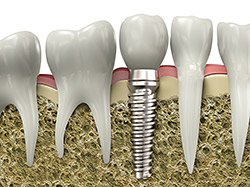

Implant restoration

Services provided by General Dentists.

If you are missing teeth, it is crucial to replace them. Without all your teeth, chewing and eating can destabilize your bite and cause you discomfort. When teeth are missing, your mouth can shift and even cause your face to look older. Implants are a great way to replace your missing teeth.

An implant is a new tooth made of metal and porcelain that looks just like your natural tooth. It’s composed of two main parts: one is the titanium implant body that takes the place of the missing root, and the other is the tooth-colored crown cemented on top of the implant. With implant treatment, you can smile confidently, knowing no one will ever suspect you have a replacement tooth.

In addition to tooth replacement, implants may be used to anchor dentures, especially lower dentures that tend to shift when you talk or chew. For patients with removable partial dentures, implants can replace missing teeth so you have a more natural-looking smile.